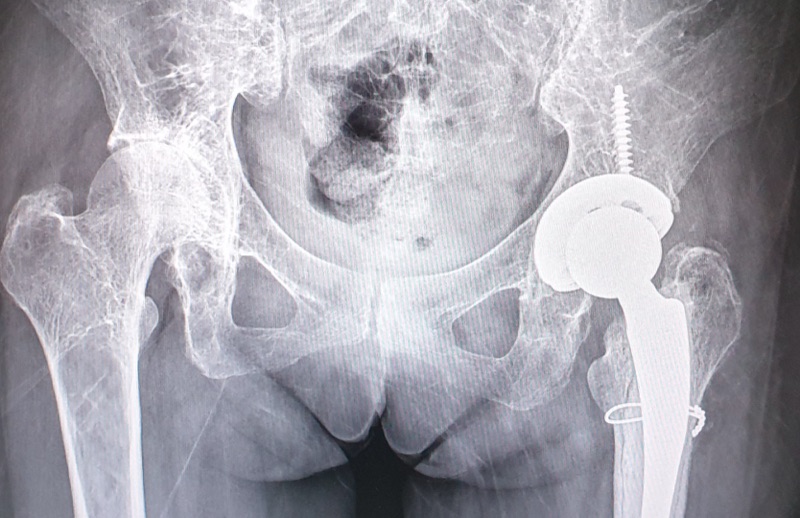

🔹 2. การรักษาด้วยการผ่าตัด (Surgical Treatment)

📌 เป็นวิธีที่ใช้มากที่สุดและให้ผลลัพธ์ดีที่สุด

📌 แพทย์จะเลือก วิธียึดตรึงกระดูก หรือเปลี่ยนข้อสะโพก ขึ้นอยู่กับสภาพของผู้ป่วย